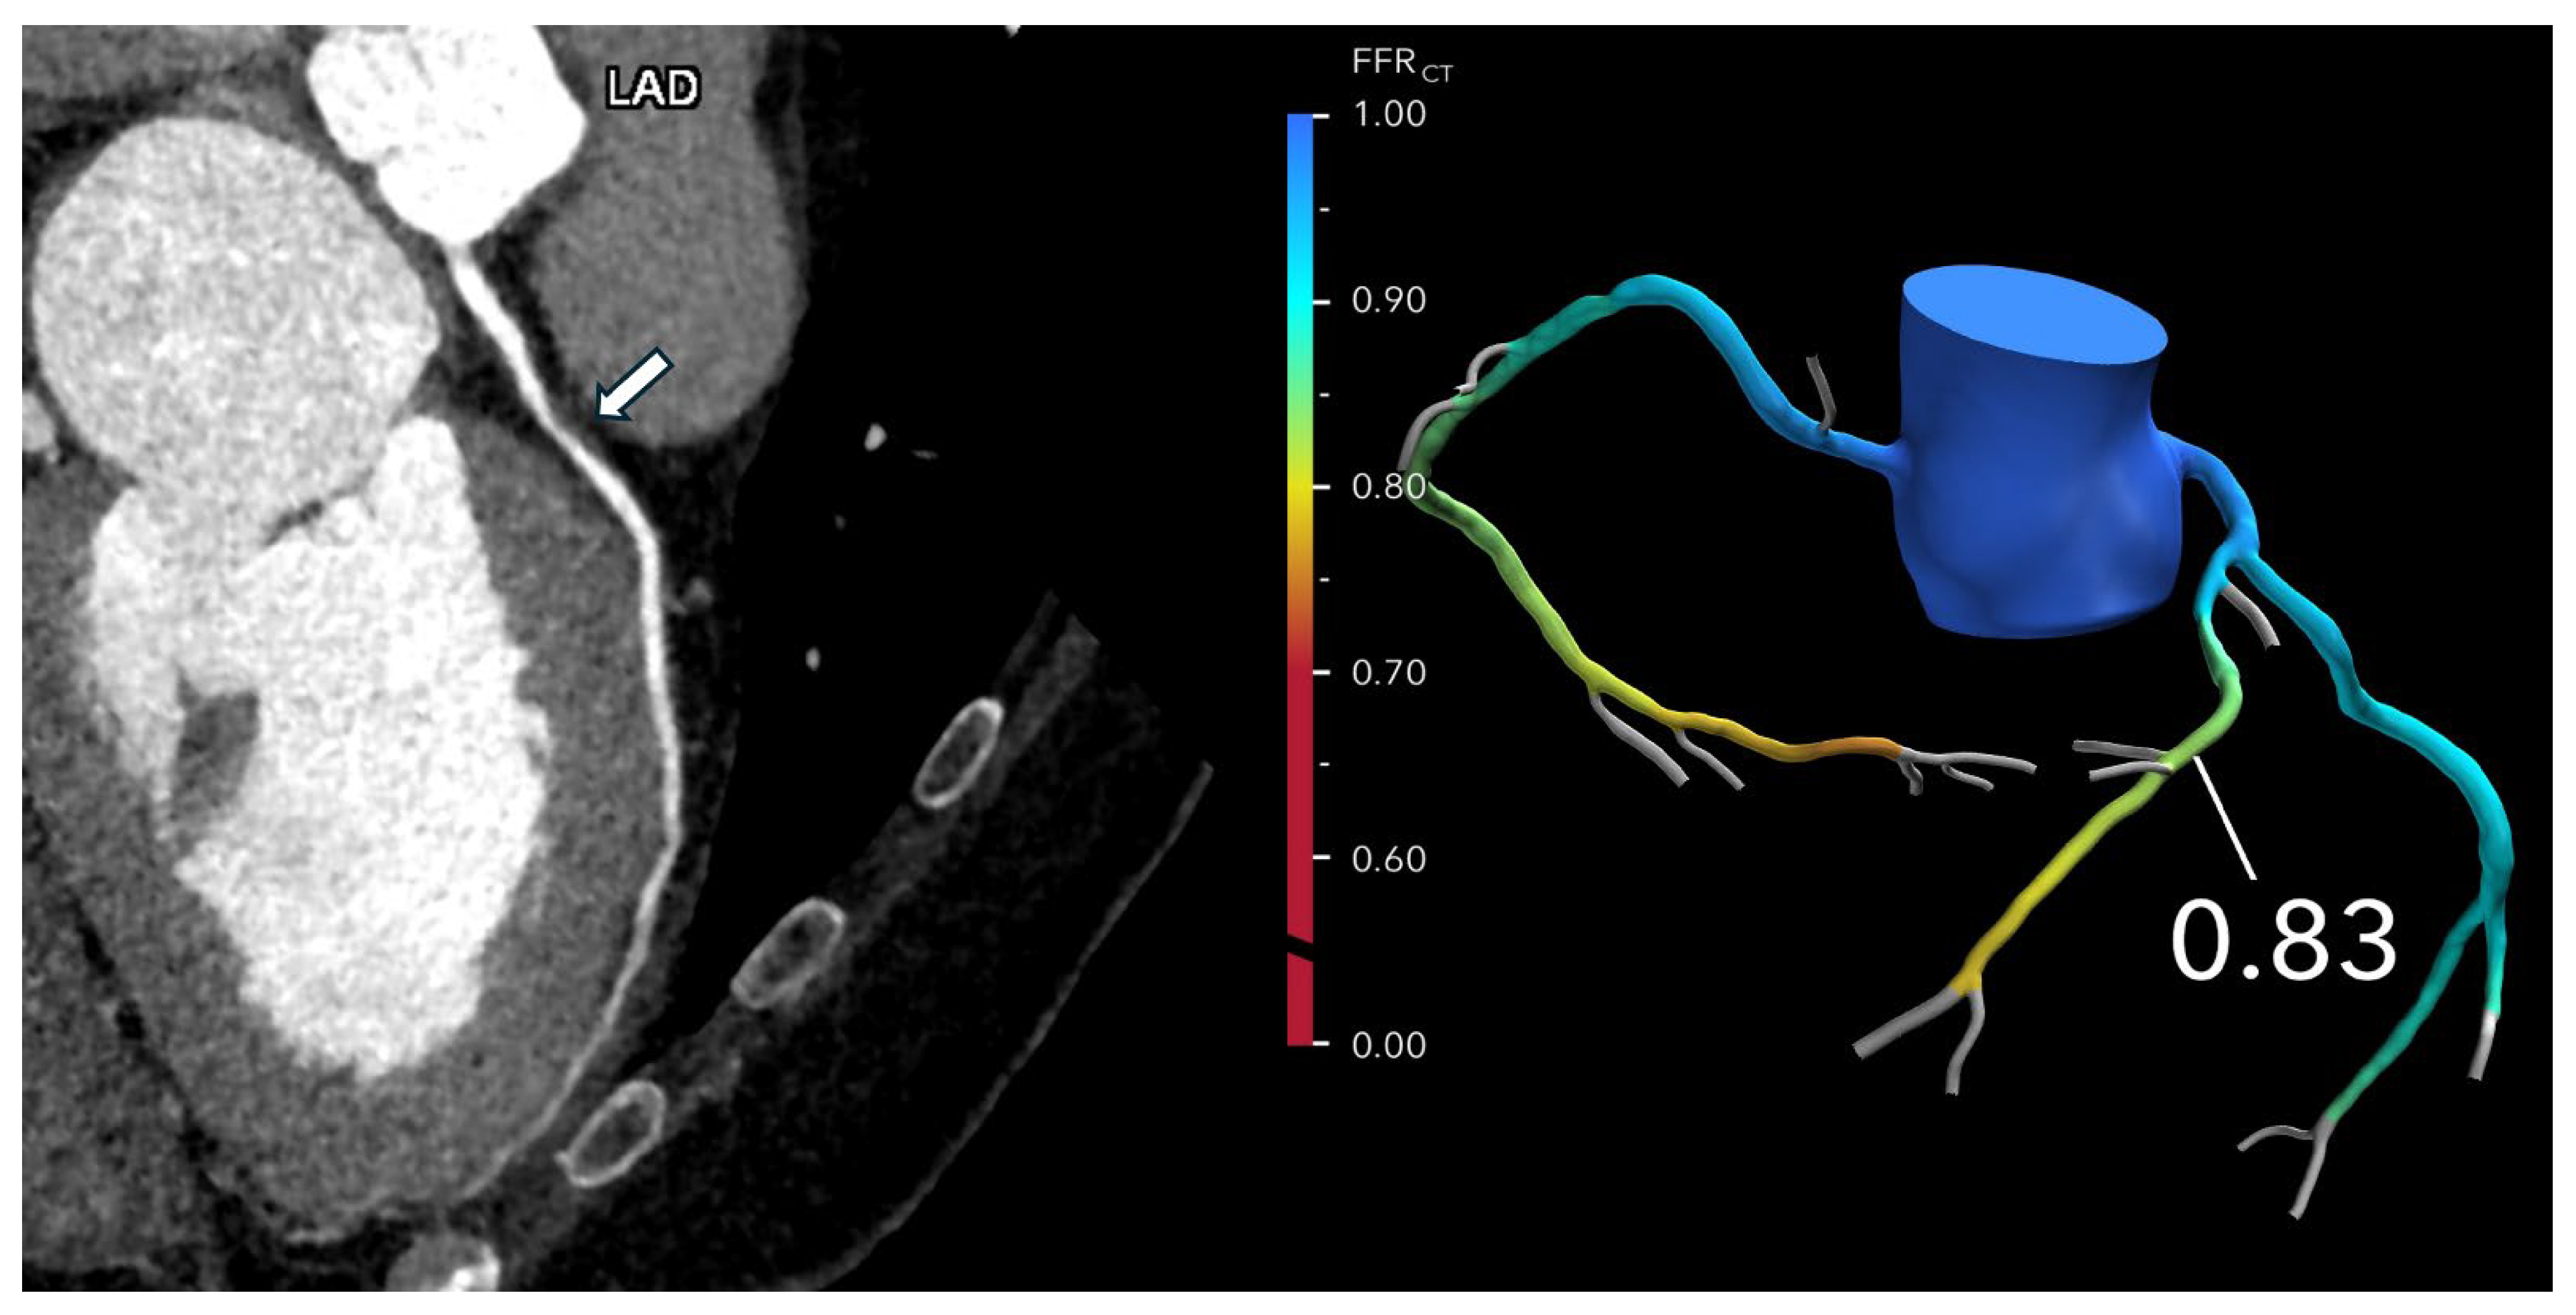

Figure 2. Optimizing treatment decisions with FFR-CT: (Left): A curved multiplanar reformatted coronary CTA image of the left anterior descending (LAD) in a 62-year-old man with atypical chest pain reveals severe stenosis (>70%) in the proximal LAD (arrow). (Right): The FFR-CT image demonstrates a value of 0.83 measured 2 cm distal to the lesion, indicating normal flow. As a result, invasive coronary angiography was deferred, and the patient was managed with medical therapy. Reprinted with permission under open access from Kasaeian et al. [6].

Kasaeian et al. reviewed the clinical applications of FFR-CT in coronary artery disease [6]. FFR-CT has been increasingly reported in the literature to yield improved accuracy in guiding patient management compared to standard coronary CT angiography (CTA). Real-world evidence of using FFR-CT in clinical practice has been validated by a number of multicenter trials proving that FFR-CT serves as a gatekeeper to invasive coronary angiography by reducing a significant number of unnecessary invasive procedures (Figure 2 and Figure 3). FFR-CT is associated with significantly lower all-cause mortality, so it can guide confidential clinical decision-making. Judicious use of FFR-CT to guide coronary CTA interpretation was discussed alongside distal-to-lesion FFR-CT measurement, showing improved concordance with invasive FFR, hence further enhancing diagnostic precision. In this study, the limitations of FFR-CT are highlighted, along with the impact of high-quality coronary CTA image acquisition and coronary calcium scores on FFR-CT performance. Future potential applications of FFR-CT, such as its implementation in the evaluation of coronary artery anomalies (Figure 4) and plaque characterization, are also reviewed. These authors also reviewed the role of FFR-CT as a reliable tool to plan percutaneous coronary intervention (PCI) and identify suitable patients undergoing coronary artery bypass grafting. Finally, they summarized the role of FFR-CT combined with risk stratification as a gatekeeper to the catheterization lab to reduce unnecessary invasive procedures without comprising clinical outcomes.